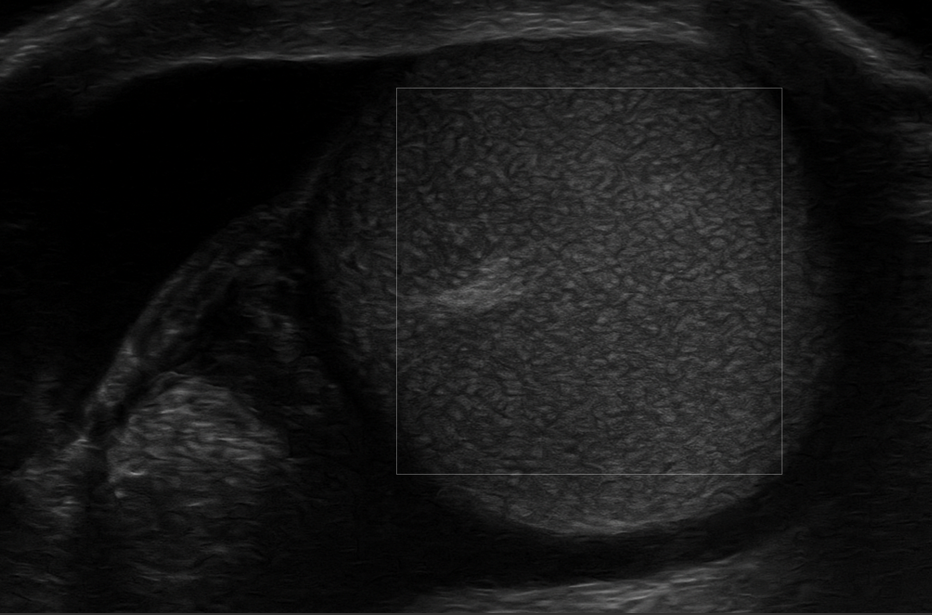

Ante la sospecha de torsión testicular, se realiza una ecografía escrotal con sonda lineal de alta frecuencia por el médico de familia en el centro de salud observándose un testículo derecho aumentado de tamaño, con ecogenicidad heterogénea y ausencia total de flujo en el estudio Doppler. Se observó también aspecto arremolinado del cordón espermático (signo del remolino), hallazgo compatible con torsión testicular aguda. La ecografía del testículo izquierdo fue normal, con flujo conservado.

Torsión testicular derecha confirmada por ecografía clínica.